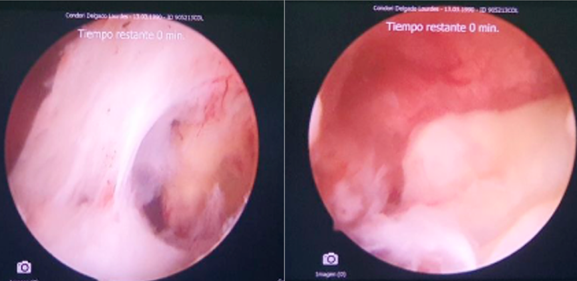

Figure 2: Left cornual region occluded by fibrous uterine synechiae, the blue arrow indicates entry into the cornual region. The red arrow indicates fibrous synechiae that almost completely occluded the left cornual region. The blue arrow indicates the uterine cavity

Figure 3: After blunt entry maneuvers, it is possible to visualize the structure corresponding to a degenerated gestational sac that is located lateral and close to the left osteum. After the cold section of the synechia, it is possible to reach the gestational sac

Figure 4: Complete extraction of the gestational sac is achieved through blunt maneuvers, grasping and retraction under hysteroscopic visualization of the gestational sac

It was decided to perform a diagnostic-surgical hysteroscopy, for which a Bettocchi-type hysteroscope (Karl Storz SE & Co KG,Tuttlingen, Germany) was used, with saline solution as a distention medium. An occlusion of the left cornual region was observed, with a fibrous adhesion lateral to the left ostium. A structure corresponding to a degenerated gestational sac was seen. A cold section of the aforementioned adhesion was performed, and the gestational sac was subsequently removed with 5 Fr grasper forceps, which emerged intact.